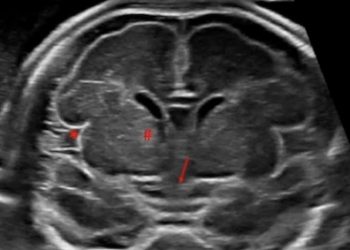

Cari soci, questo mese un nuovo video "How to do", sull'approccio avanzato all'encefalo fetale, ovvero sulla Neurosonografia. Grazie ad Andrea...